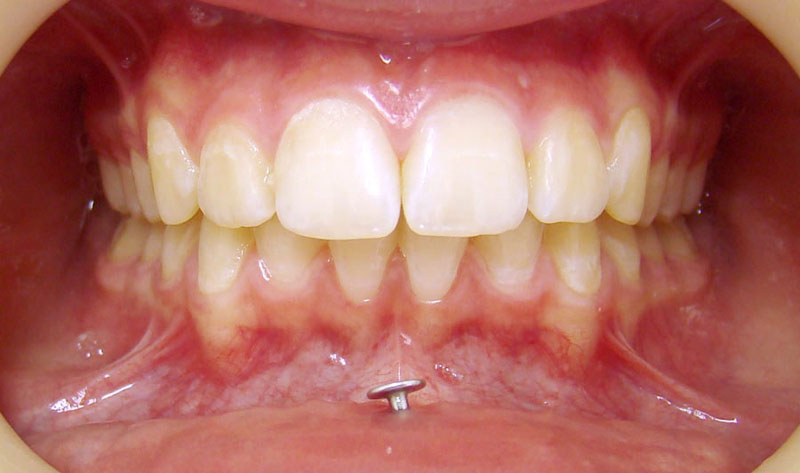

И еще одна девушка, с очень глубоким прикусом "до" и пирсингом "после"